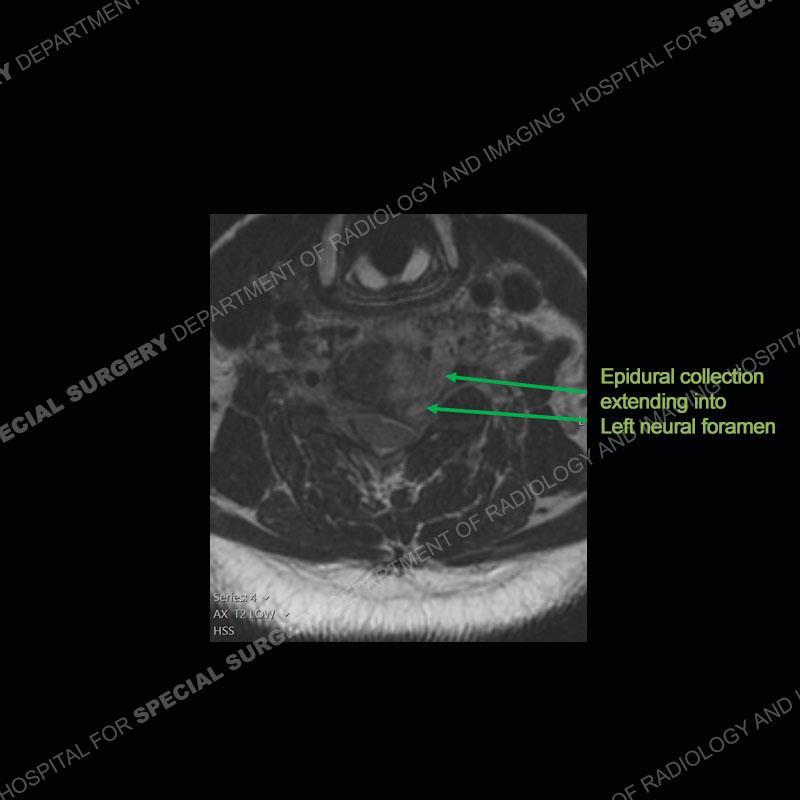

The radiographs demonstrate a prevertebral soft tissue fullness centered at C5-C6 that persists even on extension. There is a slight loss of disc height at C5-C6. The CT more readily shows the prevertebral soft tissue swelling at C5C6 where there is a punctate focus of gas. On the MRI, there is a marked amount of edema and a heterogeneous collection in the prevertebral soft tissue at C5-C6. Edema is present of the C5 and C6 vertebral bodies with a loss of the normal architecture about the disc space. A heterogeneous epidural collection has formed that causes compression of the spinal cord asymmetric to the left side and also precipitates severe left sided neural foraminal stenosis.